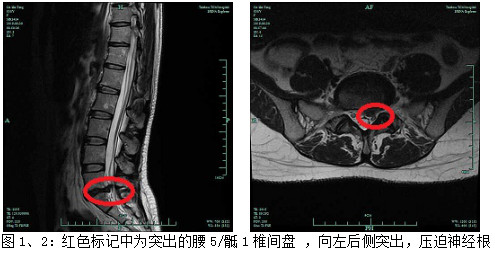

后來(lái)經(jīng)朋友介紹,被家人送至我院鄭安華副主任醫(yī)師門診就診,鄭主任仔細(xì)詢問(wèn)患者病史,并查體:脊柱尚正,生理弧度存在,腰背部腰5/骶1間隙壓痛,無(wú)叩擊痛,腰椎活動(dòng)受限,左下肢直腿抬高試驗(yàn)陽(yáng)性,約45°,右側(cè)陰性,左小腿后外側(cè)(外踝處)、跟部皮感減弱,左足趾跖屈肌力減弱。考慮“腰椎間盤突出癥”,遂建議患者行CT、磁共振檢查,2019-09-30腰椎CT、MRI示:腰5/骶1椎間盤變性伴左后突出,髓核鈣化明顯,相應(yīng)神經(jīng)根受壓(具體見圖1、2、3)。